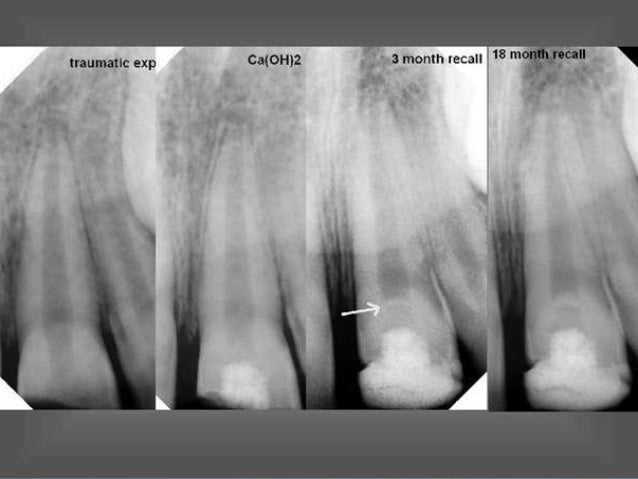

La apexificación es el tratamiento para crear un ambiente dentro del conducto radicular y los tejidos periapicales después de la necrosis pulpar, que permita la formación de una barrera calcificada a través del ápice abierto. La mejoría del conducto y del entorno apical permiten la reanudación, una vez más, del proceso interrumpido de desarrollo radicular y cierre apical. El resultado usual es el achatamiento del extremo de la raíz y poco o ningún aumento en la longitud.

La creación de un ambiente favorable para la formación de una barrera calcificada consiste en la limpieza minuciosa para eliminar bacterias y tejido necrótico del sistema de conductos, seguidas por la colocación de una pasta que permitirá la formación de una barrera calcificada en el ápice. El hidróxido de calcio se utiliza como material de obturación temporal. Es bactericida con un ph alcalino que pueda estimular la calcificación apical.